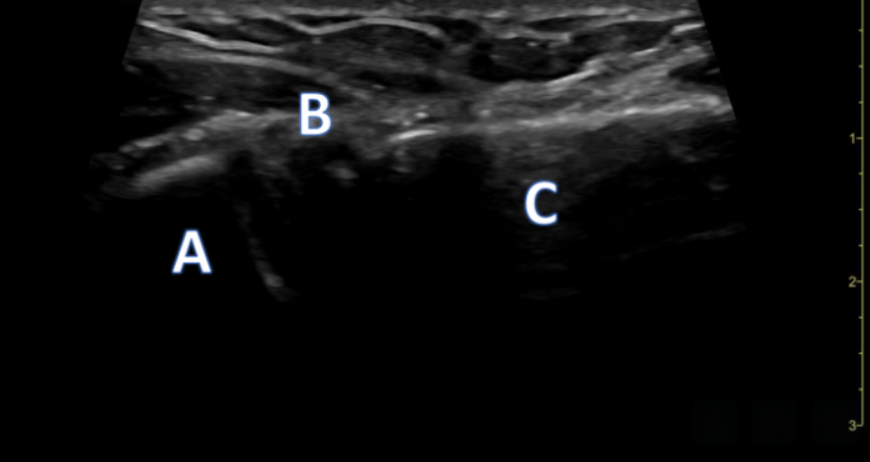

Shoulder

A 43-year-old male is complaining of right shoulder pain after a fall playing pickup soccer. You obtain an ultrasound image (Image 1) of the area with the findings below. What is your diagnosis? Can you identify the structures? A comparison image (Image 2) of the left unaffected shoulder is also provided.